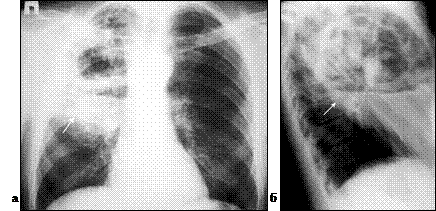

По-прежнему базовым методом подтверждения клинического диагноза бактериальной деструкции легкого остается полипозиционная рентгеноскопия и рентгенография грудной клетки, позволяющая подтвердить диагноз и определить локализацию процесса. При остром абсцессе легкого до сообщения его с бронхиальным деревом определяется правильная округлая гомогенно затемненная полость с перифокальной инфильтрацией (рис. 1). После опорожнения гнойника в дыхательные пути – полость с уровнем жидкости (рис. 2).

Рис. 2. Абсцесс верхней доли правого легкого (отмечен стрелкой). Обзорная рентгенограмма грудной клетки в прямой (а) и правой (б) боковой проекции.